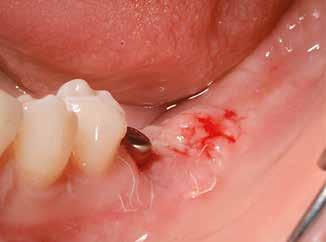

Egy 47 éves páciens jelentkezett nálunk egy alsó, hátsó foghiánnyal, ahol jelentős csontfelszívódást tapasztaltunk a moláris fogak korábbi eltávolítása miatt (1. ábra). Két implantátum körül is volt ínyrecesszió, illetve a keratinizált íny mennyisége minimális volt (kevesebb, mint 1 mm). 4 hónappal az implantációt követően ínykorrekciót végeztünk.

horizontális metszéssel kötöttük össze (2–5. ábra). A metszések hosszát és a köztük lévő távolságot minden esetben a lágyszövet augmentációhoz szükséges keratinizált szövet határozza meg. A lebeny deepitelizációját egy 15C-s szikepengével végeztük (6. ábra). Ezt követően félvastag lebenyt preparáltunk (7. ábra). A lebenyt apikálisan, az alapjáról belső, felületes metszéssel felszabadítottuk, hogy passzívan áthelyezhessük és rögzíthessük, feszülés nélkül. Meziális irányba 180 fokkal átforgattuk (8–9. ábra). A meziális papillát alagúttechnikával (tunnelling technique) készítettük elő a graft befogadására (10. ábra). Az így kialakított lebenyt a recipiens ágyban rögzítettük az újonnan kialakított vesztibulum alapjánál 5-0 nem felszívódó PTFE (Coreflon, IMPLACORE) varratokkal. A graftot behajtottuk az ínyszél alá és meziális oldalon rögzítettük PTFE varratokkal (11–14. ábra)

A műtétet követően napi kétszeri, 0,12%-os klórhexidin tartalmú szájvízzel történő öblögetést javasoltunk a páciensnek, két héten keresztül. Gyulladáscsökkentésre 8 óránként 400 mg Ibuprofént javasoltunk, három napon keresztül. A páciens elmondása szerint sem fájdalmat, sem különösebb diszkomfortot nem tapasztalt. Ezt követően, további 4 héten keresztül, 0,2%-os klórhexidin tartalmú szájvízzel történő öblögetést javasoltunk a betegnek és instruáltuk, hogy lehetőleg ne mossa fogkefével az érintett területet. A varratokat egy héttel később távolítottuk el. A donor és a recipiens terület – 10 nappal a műtétet követően – kiválóan gyógyult (15–16. ábra). Az ezt követő kontrollokat a következő időpontokban ejtettük meg: kettő, illetve négy héttel a műtét után, majd három, hat és tizenkét hónappal később, ezt követően pedig félévente (17–20. ábra). Minden kontroll alkalmával professzionális fenntartó kezelést végeztünk a területen.